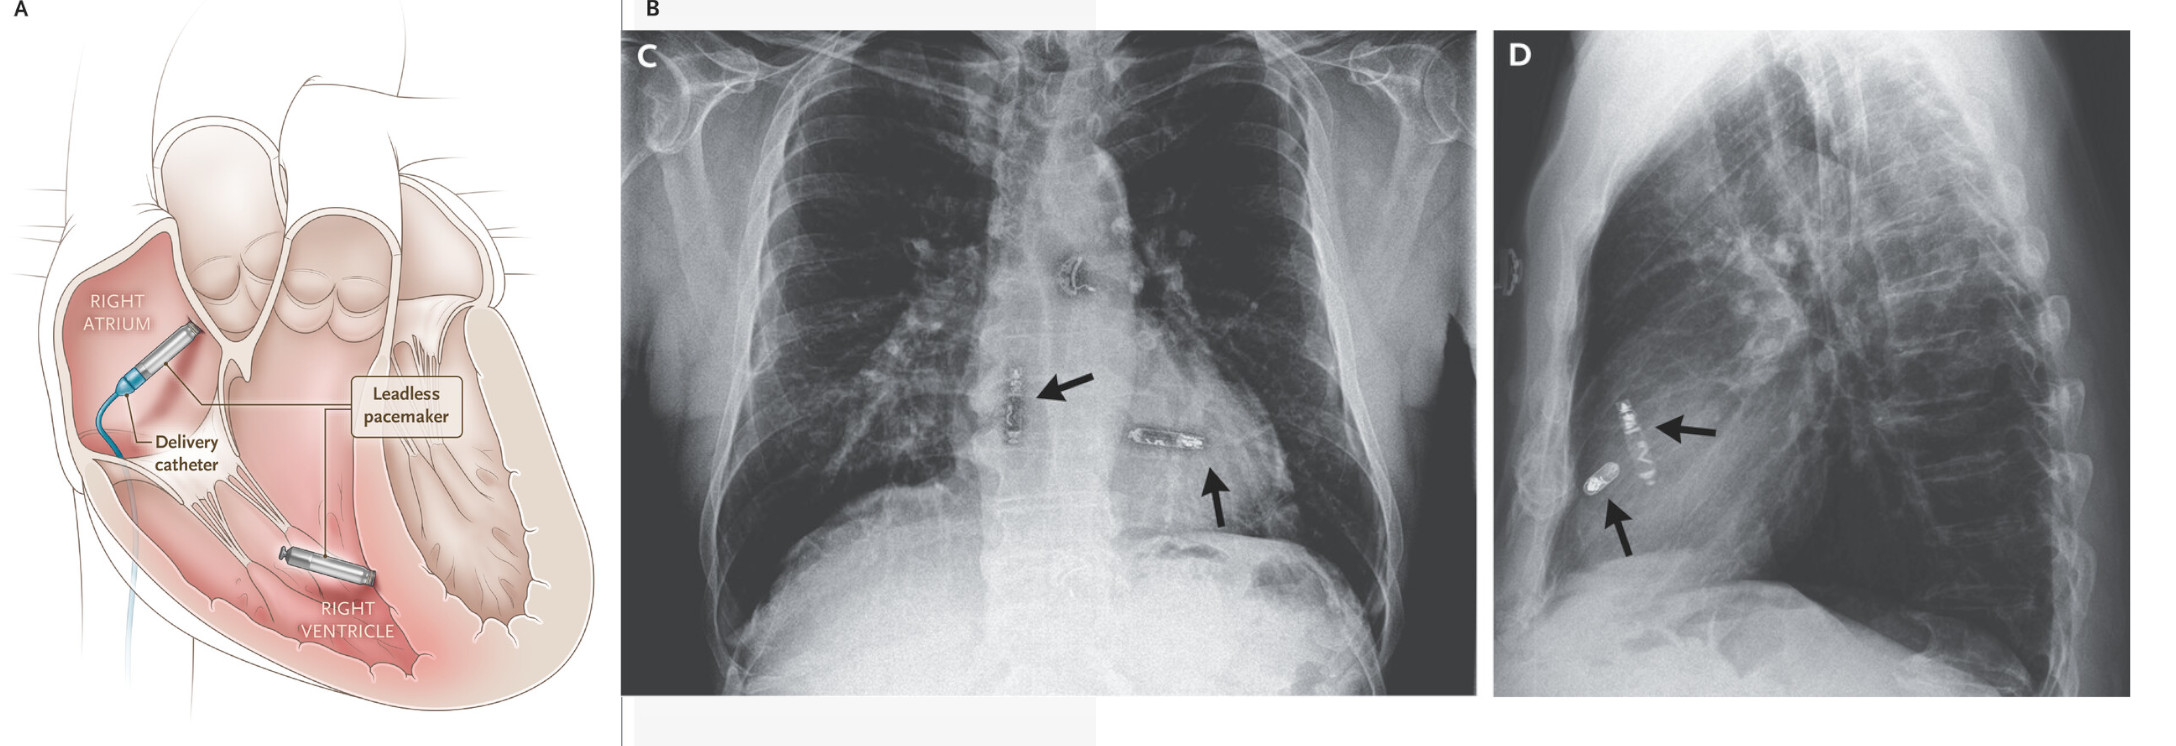

Dual chamber leadless pacemaker

dual_llp.jpg

Knops RE, Reddy VY … Aveir DR i2i Study Investigators. A Dual-Chamber Leadless Pacemaker. N Engl J Med. 2023 Jun 22;388(25):2360-2370. doi: 10.1056/NEJMoa2300080.